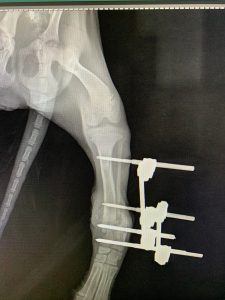

- Liječenje prijeloma kostiju, uključujući intraartikularne frakture

- Korektivne osteotomije za ispravljanje deformiteta